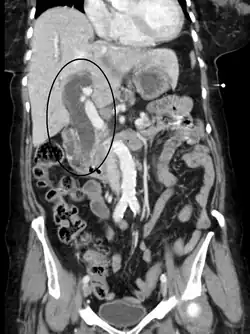

Imaging

Medical imaging such as ultrasound, CT scan, and HIDA scan are useful for detecting bile-duct blockage.[41]